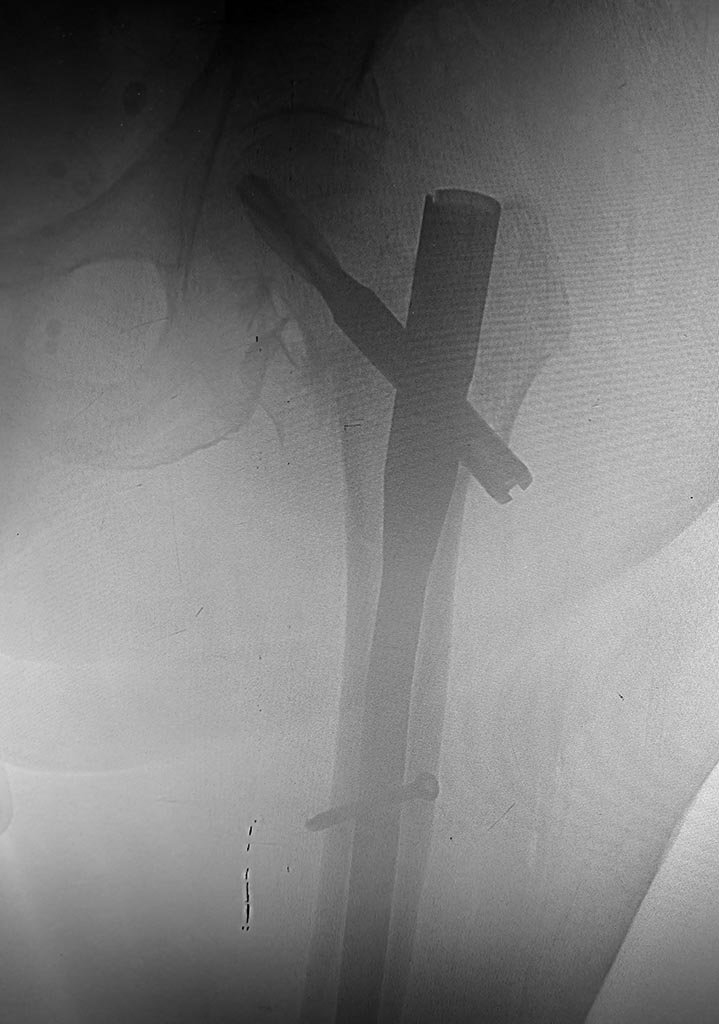

Использовали полер-спицы для форммрования канала и винт Шанца для

удержания отломка б.вертела при заведении гвоздя.